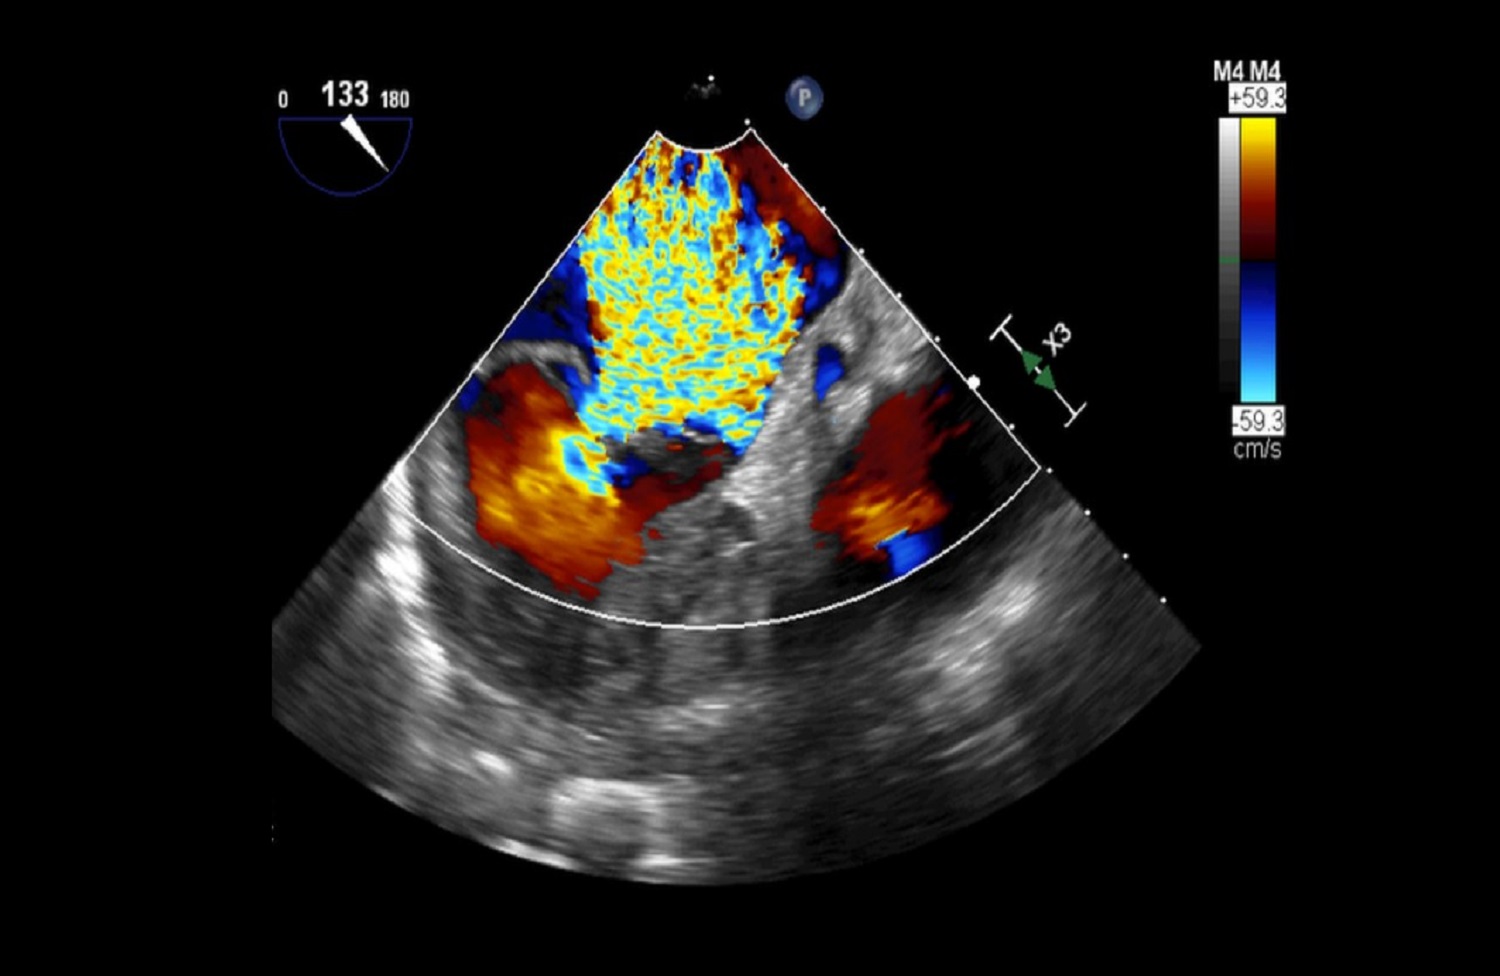

Pracownia Echokardiografii

Pracownia Echokardiograficzna Kliniki posiada Akredytację Klasy C (najwyższy poziom referencyjny) przyznaną przez Zarząd Sekcji Echokardiografii Polskiego Towarzystwa Kardiologicznego. W ciągu roku wykonywanych jest tu łącznie ponad 3600 badań echokardiograficznych przezklatkowych, przezprzełykowych i prób z dobutaminą.

W Pracowni badani są pacjenci hospitalizowani w oddziałach Kliniki oraz we wszystkich pozostałych Klinikach Szpitala Klinicznego Dzieciątka Jezus, a także pacjenci ambulatoryjni kierowani z Poradni Kardiologicznej, Nadciśnienia Tętniczego, Przeciwzakrzepowej, Transplantacyjnej i Nefrologicznej Szpitala. Pracownia ukierunkowana jest na diagnostykę zatorowości płucnej, nadciśnienia płucnego, wad zastawkowych, infekcyjnego zapalenia wsierdzia oraz dysfunkcji lewej komory.

Dzięki wykwalifikowanemu personelowi i nowoczesnemu sprzętowi w Klinice wykonywane są również przezskórne zabiegi zamknięcia ubytków przegrody międzyprzedsionkowej typu II oraz drożnego otworu owalnego, pod kontrolą echokardiografii dwu – i trójwymiarowej.

Na podstawie badań z zastosowaniem przezprzełykowej echokardiografii trójwymiarowej w pracowni kwalifikuje się również pacjentów z ciężką niedomykalnością mitralną w mechanizmie wypadania płatka mitralnego do nowatorskich zabiegów małoinwazyjnej przezkoniuszkowej naprawy zastawki bez użycia krążenia pozaustrojowego. Efektem współpracy z Oddziałem Kardiochirurgii Szpitala Medicover była możliwość monitorowania echokardiograficznego przezprzełykowego dwóch pierwszych w Polsce zabiegów naprawy zastawki mitralnej z użyciem robota chirurgicznego da Vinci.

Echokardiografia przezklatkowa przezprzełykowa obciążeniowa z pełnym obrazowaniem dopplerowskim i trójwymiarowym.